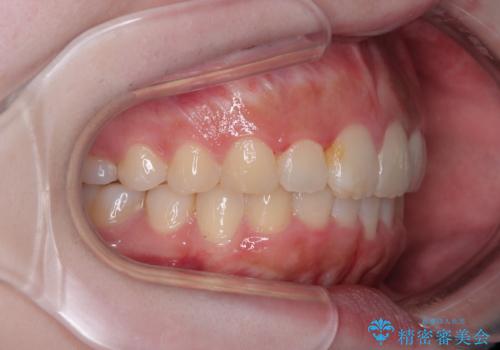

前歯のデコボコをインビザラインできれいに整える

前歯の捻れを改善するとともに、口元が少しでも引っ込むように治療計画を立て、仕上げることができました。

長時間の装着や、定期的な来院がままならず、想定よりも長期間の治療となってしまいました。